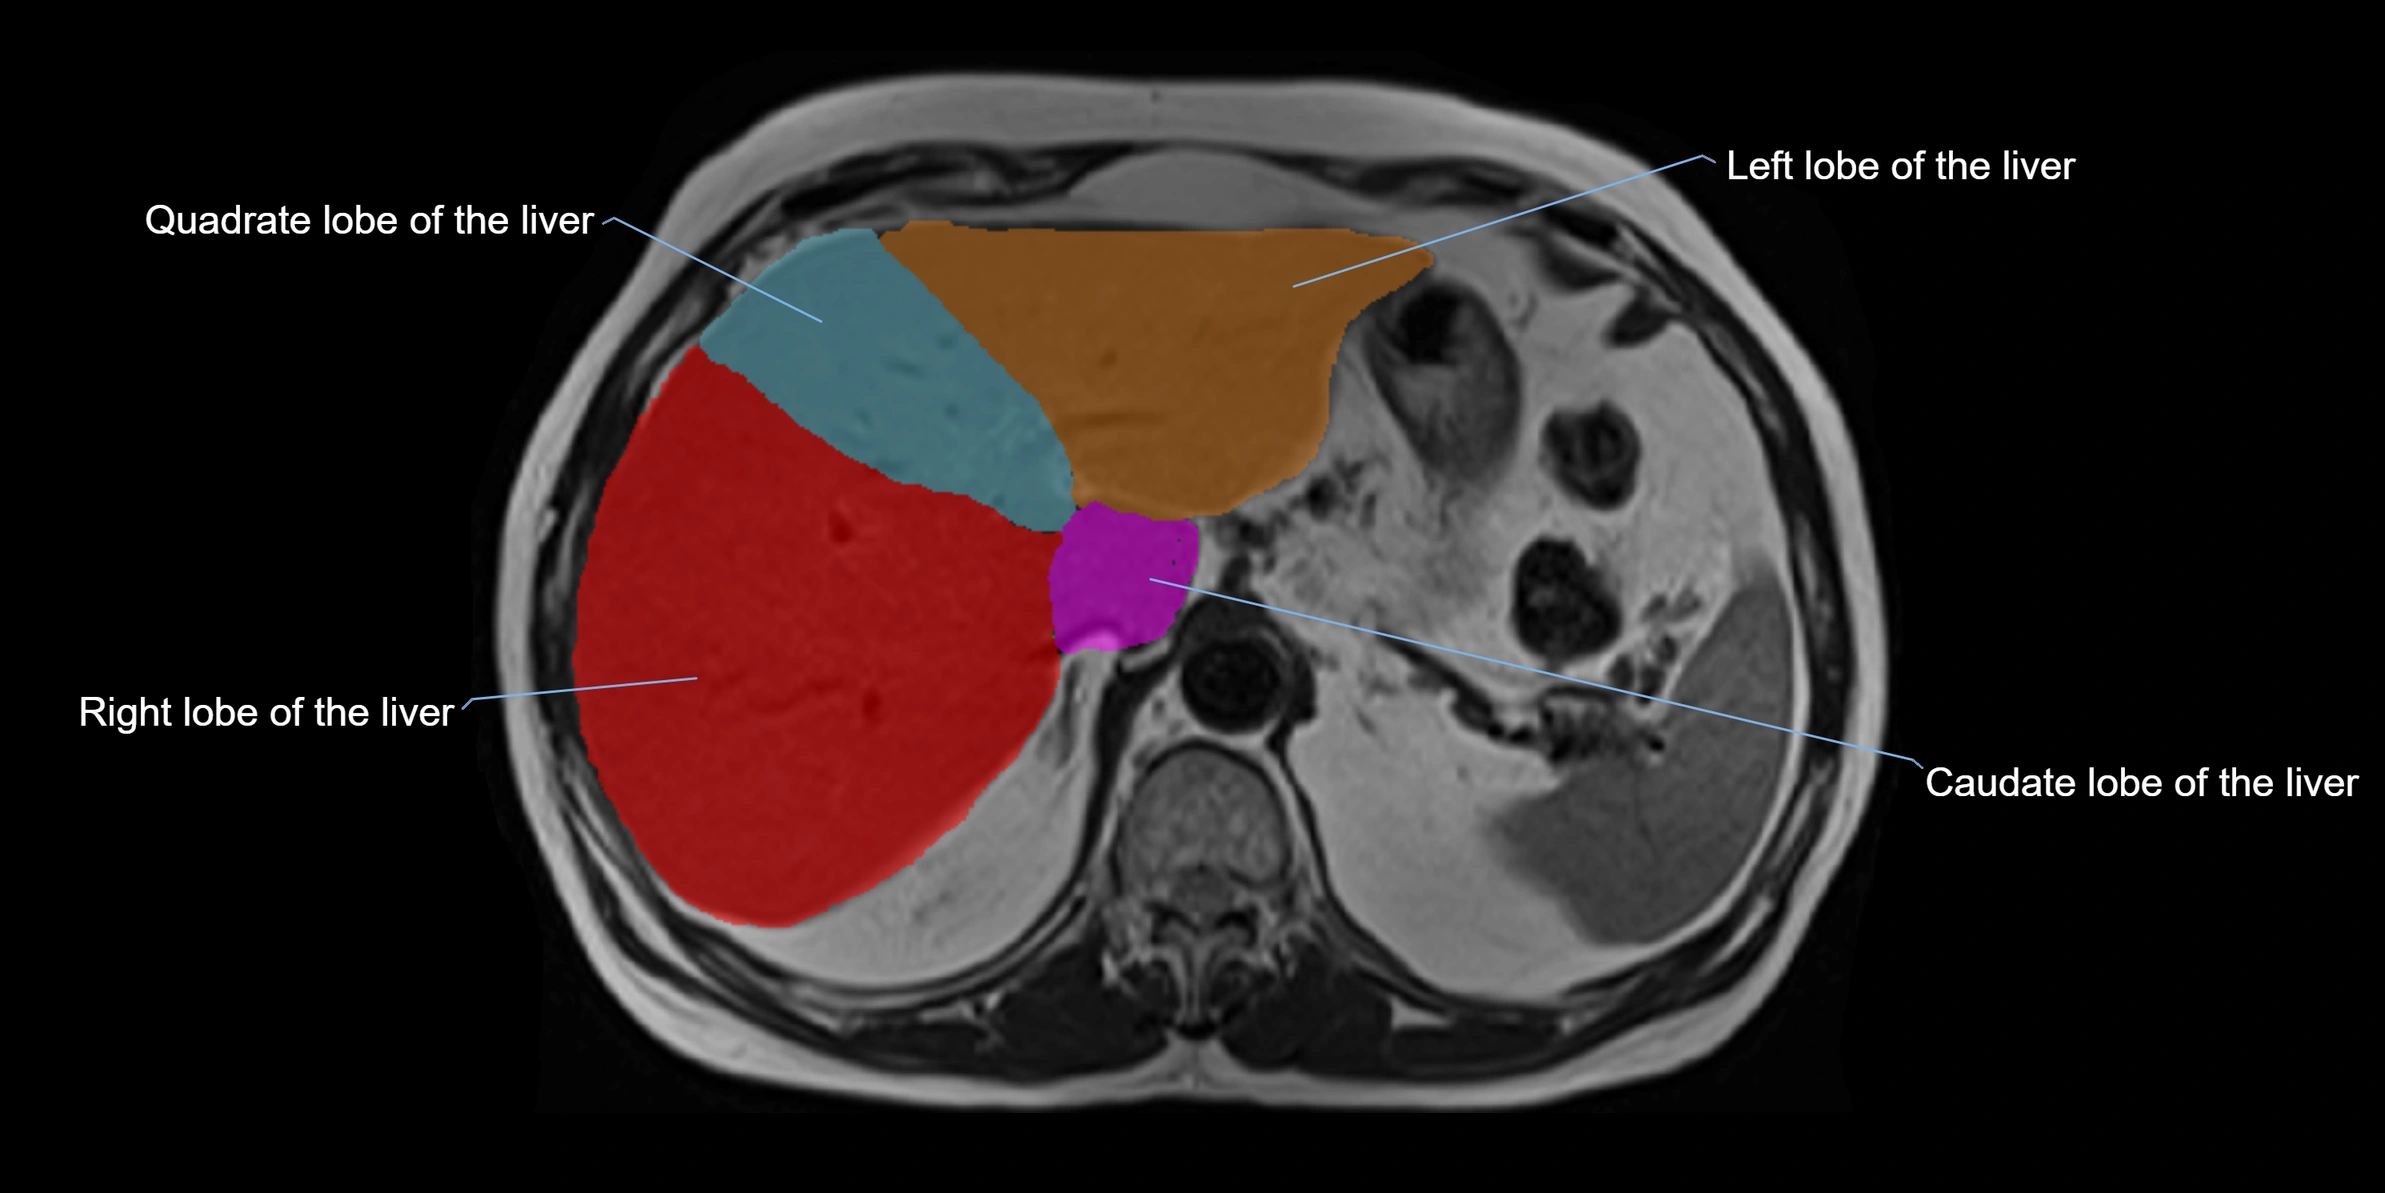

The caudate lobe of the liver is a distinct anatomical subdivision of the liver, designated as segment I in Couinaud’s classification. It lies on the posterior surface of the liver, between the fissure for the ligamentum venosum (left boundary) and the groove for the inferior vena cava (IVC) (right boundary). Superiorly, it is related to the posterior liver surface, and inferiorly it is separated from the left lobe by the porta hepatis.